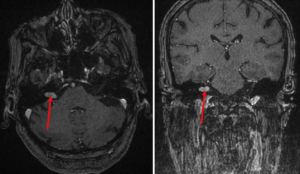

Tanı genellikle hastanın yakınmalarından ve muayene bulgularından kuşkulanan doktorun bazı işitme ve denge testlerini yaptırması, manyetik rezonans görüntüleme ve bilgisayarlı tomografi gibi ileri görüntüleme tetkikleri yaptırması ile konulur (Şekil 2).

Şekil 2. Orta-ileri yaşta bir kadın hastamızda manyetik rezonans görüntüleme (MR) ile görüntülenmiş denge siniri tümörü (vestibüler schwannoma) kırmızı oklarla işaretlenmiştir.